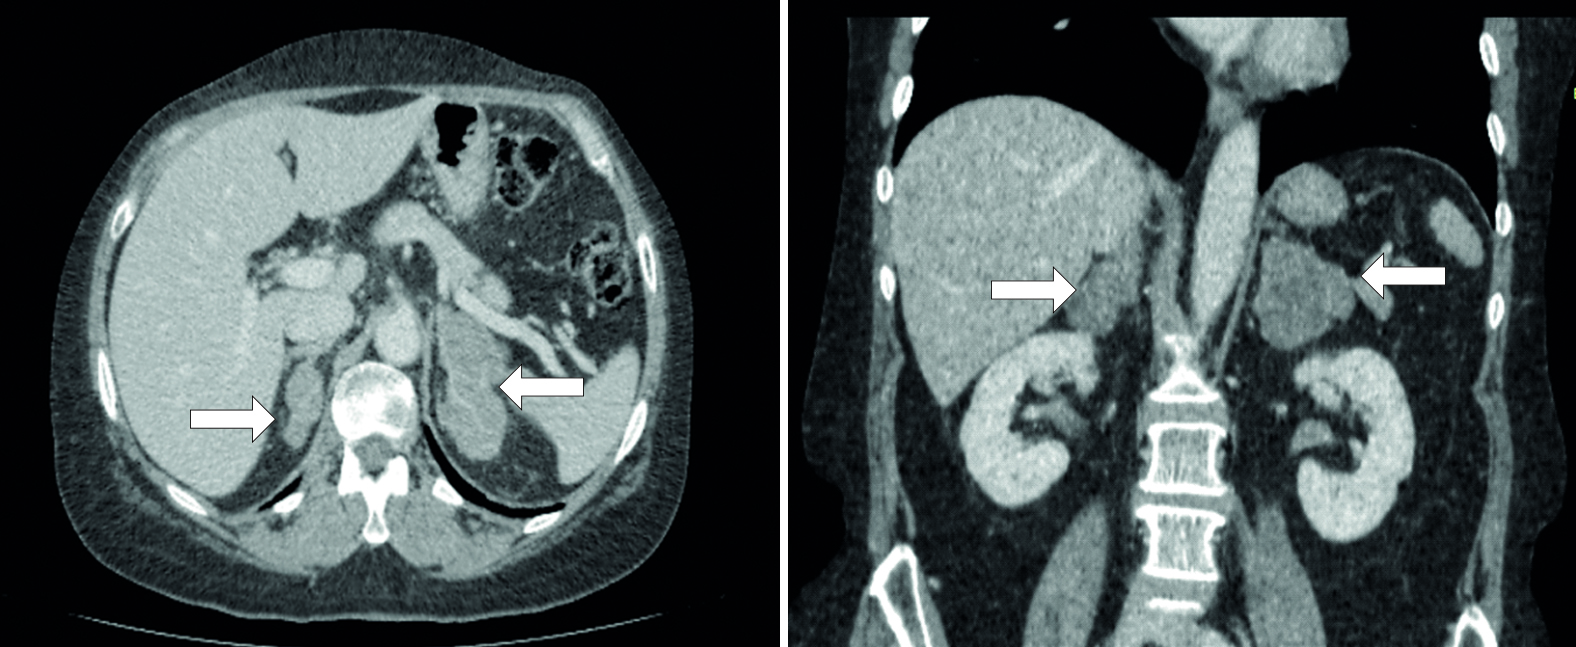

Визуализирующий фенотип БМНГ (рисунок 1) был представлен множественными узловыми образованиями в обоих надпочечниках (1 наблюдение), множественными узловыми образованиями в одном надпочечнике и одиночным узлом к контрлатеральной железе (2 наблюдения), односторонним многоузловым изменением с гиперплазией противоположного надпочечника (1 наблюдение), двусторонней одноузловой гиперплазией надпочечников (7 наблюдений).

Рисунок 1. Аксиальный (1) и корональный (2) срезы с изображением правого и левого надпочечников (нативная фаза) с двусторонней макронодулярной гиперплазией.

Figure 1. Axial (1) and coronal (2) views of the right and left adrenal glands (native phase) with bilateral macronodular hyperplasia.

Среднее значение плотности (правого и левого надпочечника) в нативную фазу находилось в диапазоне -4 +7 HU, в венозную фазу +18 +53 HU, в выделительную фазу +5 +18 HU. Абсолютный и относительный коэффициент вымывания на 10–15 мин составил 56,3% – 88,9% и 53,8% – 80% соответственно.